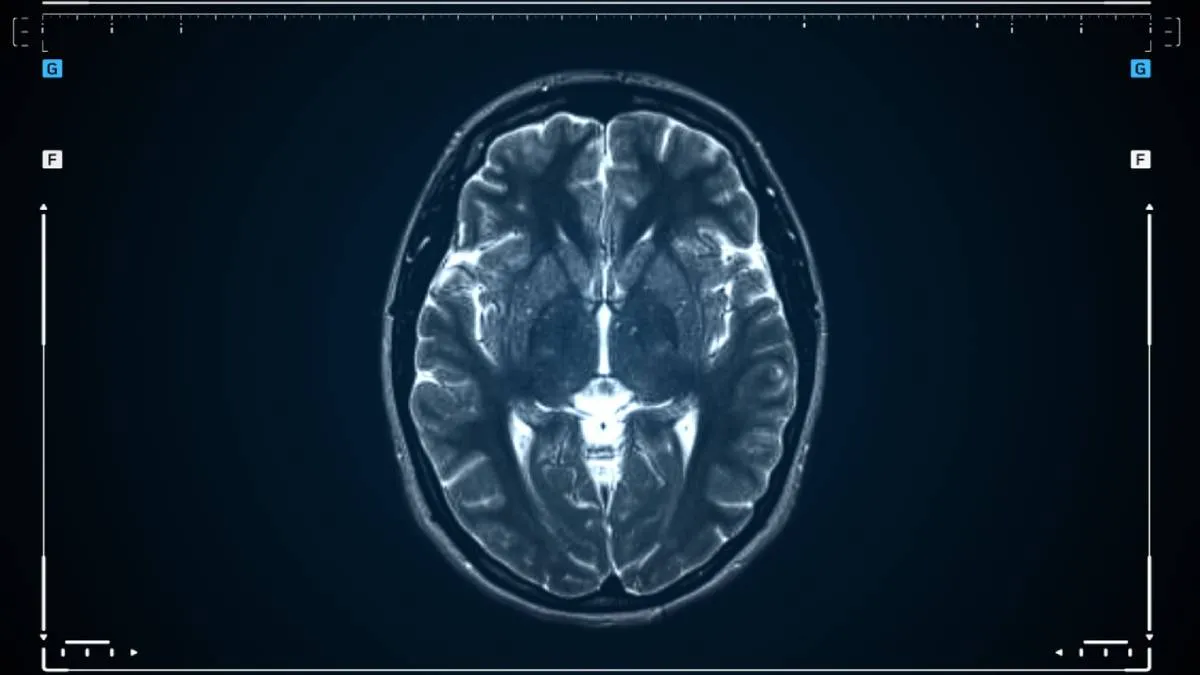

Use magnetic fields and radio waves to produce detailed images of brain structures, offering superior detail for tumor assessment.